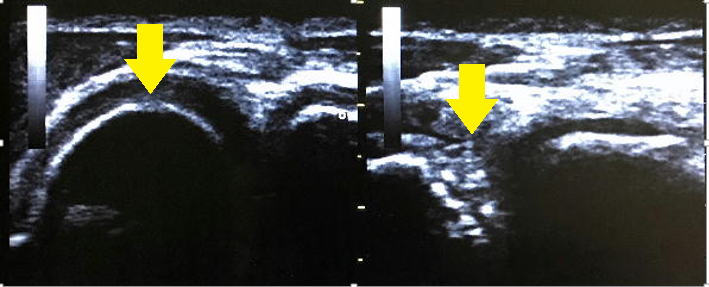

※画像:左が健側、右が患側です。

【症例1 離断性骨軟骨炎(野球肘外側型)】

中学3年生。投球することがほとんどなく、今まで肘を痛めたこともなかった選手が前日ピッチングをして初めて肘の痛みを感じて来院。

痛みは無くとも肘の外側で上腕骨小頭部に骨輪郭の乱れを認めるケースが多い症例。